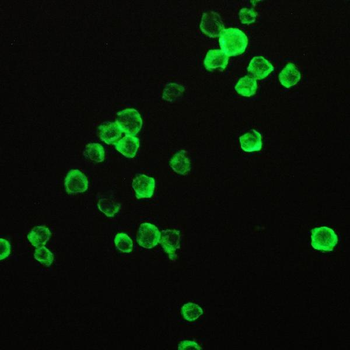

50 μl, 100 μl, 200 μlFKBP52 Antibody: APC [orb147210]

ICC, IF, IHC

Canine, Hamster, Human, Mouse, Rat

Mouse

Monoclonal

APC

100 μgFKBP52 Antibody: Biotin [orb147211]